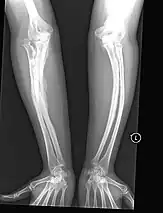

Metal rods can be surgically inserted in the long bones to improve strength, a procedure developed by Harold A. Sofield when he was Chief of Staff at Chicago's Shriners Hospitals for Children, a hospital that offers orthopedic care and surgery to children regardless of their family's ability to pay.[115] Large numbers of children with OI came to Shriners, and Sofield experimented with various methods to strengthen their bones.[116] In 1959, with Edward A. Millar [sic], Sofield wrote a seminal article describing a three-part surgery that seemed radical at the time: precisely breaking the bones ("fragmentation"), putting the resulting bone fragments in a straight line ("realignment"), then placing metal rods into the intramedullary canals of the long bones to stabilize and strengthen them ("rod fixation").[117] His treatment proved useful for increasing the mobility of people with OI, and it has been adopted throughout the world—it became standard surgical treatment for severe OI by 1979, in which year David Sillence found that ≈2⁄3 of the patients he surveyed with OI type III had undergone at least one rodding surgery.[42]: 108

Rodding surgery is often done with the hope that it will offer a path to ambulation, walking, to patients with moderate or severe OI. A 2020 review in The Journal of Bone and Joint Surgery (JB&JS) found it remains broadly popular: ≈2⁄3 of people with OI types III and IV (severe OI) have undergone some form of rodding surgery in their lives, at a mean age of 4+1⁄10 and 7+1⁄2 years respectively;[25]: Table I one possible explanation for a tendency towards earlier intervention in type III is that one half of affected children could not walk at all without the surgery, as their limbs were more bowed, so surgery was sought sooner.[25]

In those with type III OI who had undergone rodding surgery, 79.5% had the femurs and tibias of both legs rodded.[25]: Table I The most common form of rods used are intramedullary (IM) rods, some of which, such as the Fassier–Duval IM rod, are telescoping, meaning that they are designed to grow as the child grows, in an attempt to avoid the necessity of revision surgeries.[118] Telescoping IM rods are widely used,[119] and the common Fassier–Duval IM rod is designed to be used to rod the femur, tibia, and humerus.[120]: 1 The surgery involves breaking the long bones in between one and three (or more)[119]: Figure 4 places, then fixing the rod alongside the bone to keep it straight.[120]: 11

While telescoping IM rods are intended to grow along with both the femur and tibia in developing children; surgeons have a preference to use non-telescoping IM rods, such as Rush rods, in the tibia, which grows less comparatively—the JB&JS review found that while 69.7% of femurs were treated with telescoping IM rods, only 36.9% of tibiae were.[25]: Table IV